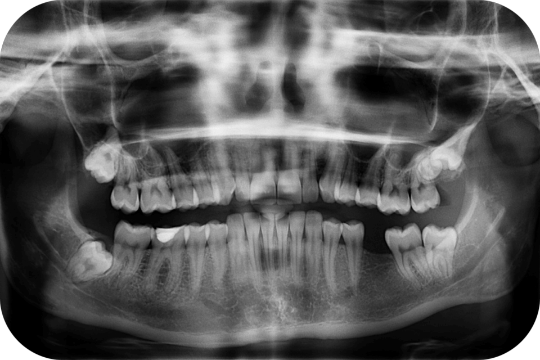

Panorámica